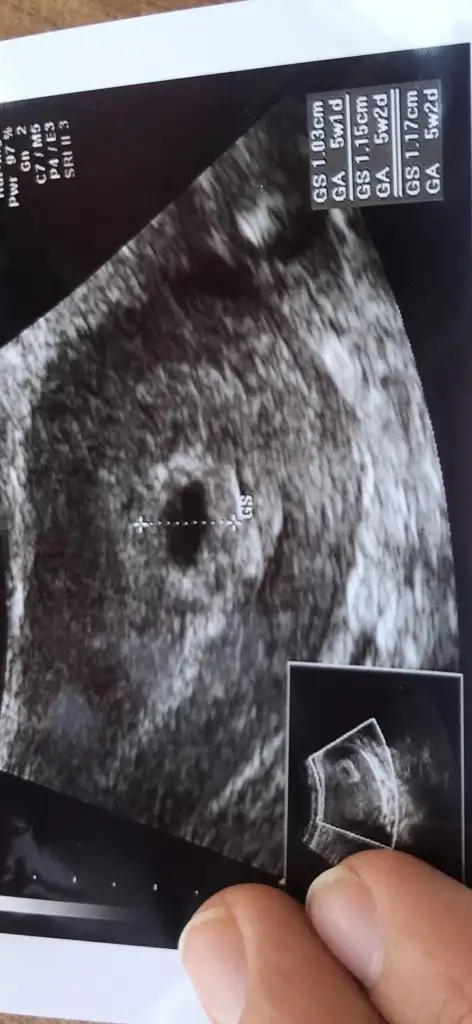

Kızlar kesem oluşmuş bunu sizinle paylaşmak istedim içinde nokta gibi yolk var dedi bebek oluşmaya başlamış sanırım

• A9EAFB1D-1CE4-43D9-AC10-816F8AEED2CD.webp

A9EAFB1D-1CE4-43D9-AC10-816F8AEED2CD.webp

14,4 KB · Görüntüleme: 51